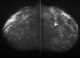

Colloid carcinoma of breast